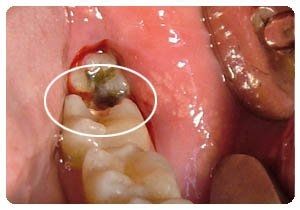

小孩子虫牙的发病最开始是在牙冠上面,要是不能及时的进行治疗,就会因为病变的持续发展因而形成龋洞。孩子的乳牙期间特容易产生,产生虫牙了,家长需要及时带孩子到正规的口腔进行治疗,以防虫牙继续严重。那么,小孩虫牙治疗要多少钱?>>点击在线咨询详情<<